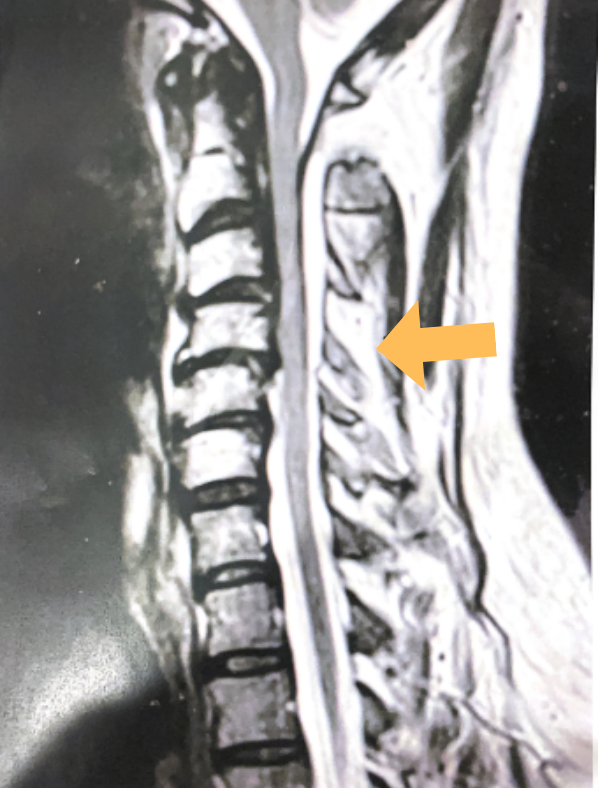

Revision Surgery Treats Intractable Neck Pain & Cervical Deformity

Author: Benjamin R. Cohen M.D., F.A.A.N.S., F.A.C.S., Read More!